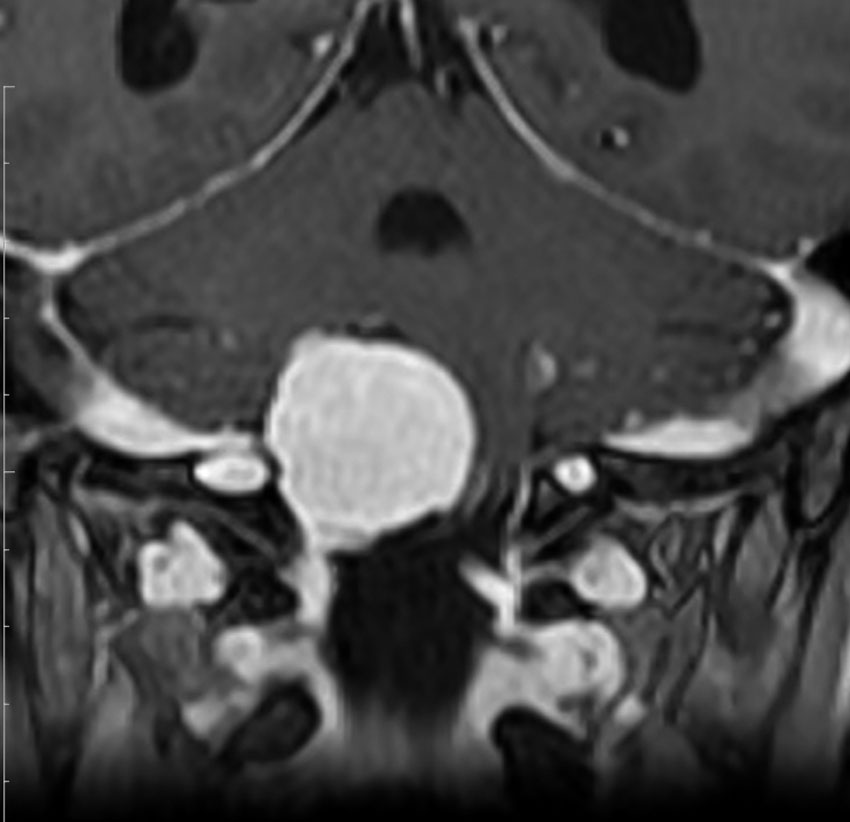

眼窩内腫瘍です。視神経を包むし神経鞘から発生して,視神経鞘に沿って進展して増大します。視神経を圧迫してゆっくり症状が出ます。片目の視力が落ちるというのが症状ですが気づかれず発見が遅れることが多いでしょう。眼底検査で,初期には視神経乳頭 optic discの腫れが見られ,視力が悪化していくと視神経萎縮となります。眼底検査で動静脈シャントが見られるのも特徴的で,視力低下と視神経萎縮と併せてHoyt-Spencer triadと言われました。視力がほぼ消失するまで腫瘍が増大すると,眼球が前に押されて,眼球突出 exophhalmus, enophthalmus という症状が出ます。

治療は手術摘出ですが,この腫瘍を摘出するとほぼ確実に片眼の視力を消失します。ですから視力が無くなるまで手術は待機するという考え方が一般的です。数年以上視力があまり低下しないで腫瘍も増大せず経過する患者さんもいます。視力温存目的で治療するなら,視力の良いうちに定位放射線治療を行うべき疾患です。だからといって何でも定位放射線治療をすればよいというものではありません。問題は,視神経管から鞍結節に腫瘍が伸展している例があるということです。ここを放置すると反対側の健常な眼の視力が侵されることになりかねないので慎重に判断します。

比較的急速に視力低下して手術摘出した例

右目が暗いという症状で発症して,眼科では視神経乳頭腫脹とわずかな視野欠損だけで発症した患者さんです。3年間観察されましたが,その間には眼底所見も視力 Vd 1.2 も変化がなかったとの眼科からの報告です。そのすぐ後で患者さん本人は,右目が暗くなる回数が増え、視野狭窄があり軽い眼球突出,まわりがぼやけてますが中心は1.0見える状態との訴えで相談を受けました。主治医の先生の方針では経過観察ということで,まだ視力も良いので私もそうした方がよいと同意したのですが,その後半年くらいで視力が手動弁まで低下してしまいました。眼球運動と右眼球を温存するために腫瘍を摘出しました。

左側は,摘出標本の輪切りの写真です。この部位は腫瘍の発生した部位ではありません。一番外側にみえるのは視神経鞘 optic sheathという膜です。その内側が髄膜腫で,その内側が視神経です。すなわち髄膜腫は,視神経鞘と視神経の間のくも膜下腔を,這うように伝わって増殖伸展しています。このくも膜下腔には視神経への栄養動脈や網膜動脈も入っているので,この腫瘍だけを視神経や細動脈を傷つけずに摘出することはできないのです。